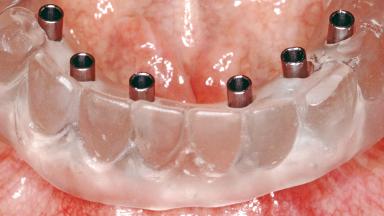

Conventional Loading of Six Implants in the Mandible and Final Restoration with a Full-Arch Metal-Ceramic FDP

# of Implants 6

Type of Implants One-Piece

Attachment One-Piece

Abutment Type Standard

Prosthesis Type FDP

Retention Screw-retained, with 4 or more splinted implants Screw-retained, with 4 or more splinted implants